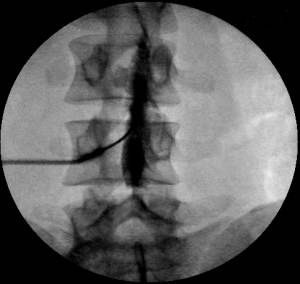

Для того, чтобы окончательно убедиться в правильности нахождения иглы в перидуральном пространстве вводится небольшое количество рентгенконтрастного вещества.

Контрастированное перидуральное пространство имеет характерный вид (перидурограмма).